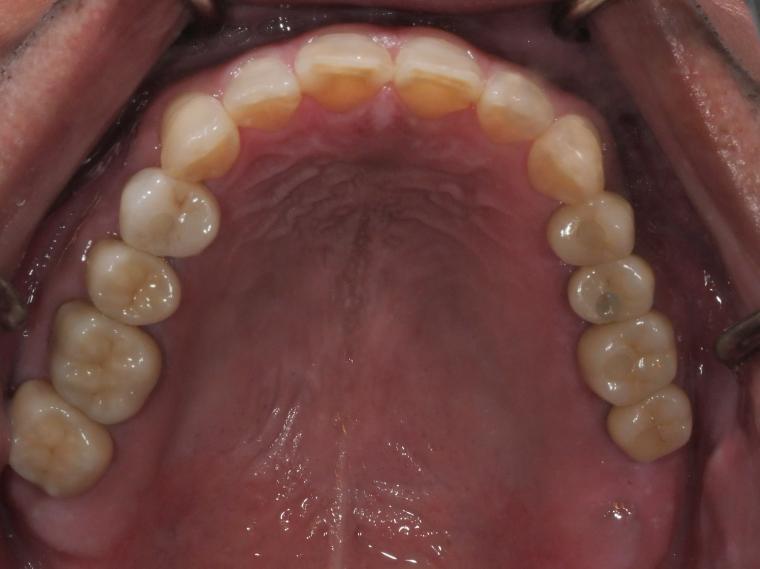

上顎臼歯部欠損症例

AFTER

41歳男性/上5本欠損/インプラント埋込手術

上5本が虫歯になってしまった為治療をすることになった患者さんです。

虫歯が進行していて、歯を保存出来なかったため歯を抜いて人工の骨を足してからインプラントを

5本埋込した患者さんです。

現在も定期検診で拝見させていただいてます。